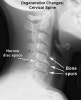

- X-ray

척추의 퇴행변화와 동적 척수 압박 소견을 확인

굴곡 또는 신전시에 추체간에 전위가 일어나거나 각변형이 일어나게 되면서 척추관이 좁아질 수 있습니다.

퇴행되고 강직된 분절 상위에서 과도한 움직임을 흔히 볼 수 있으며 주로 고령층의 C3-4간이 흔합니다.

X-ray : 경추 척수증(Cervical myelopathy)